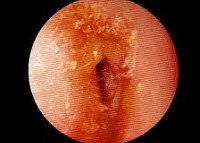

Наружный отит - воспаление наружного слухового прохода и ушной раковины, также известное под названием ухо пловца.

Симптоматика определяется причиной возникновения отита и локализацией процесса. Наиболее частыми симптомами являются зуд и/или боль внутри наружного слухового прохода, боль при надавливании на козелок, выделение гноя из пораженного уха. Также могут возникать симптомы общей интоксикации (слабость, температура).